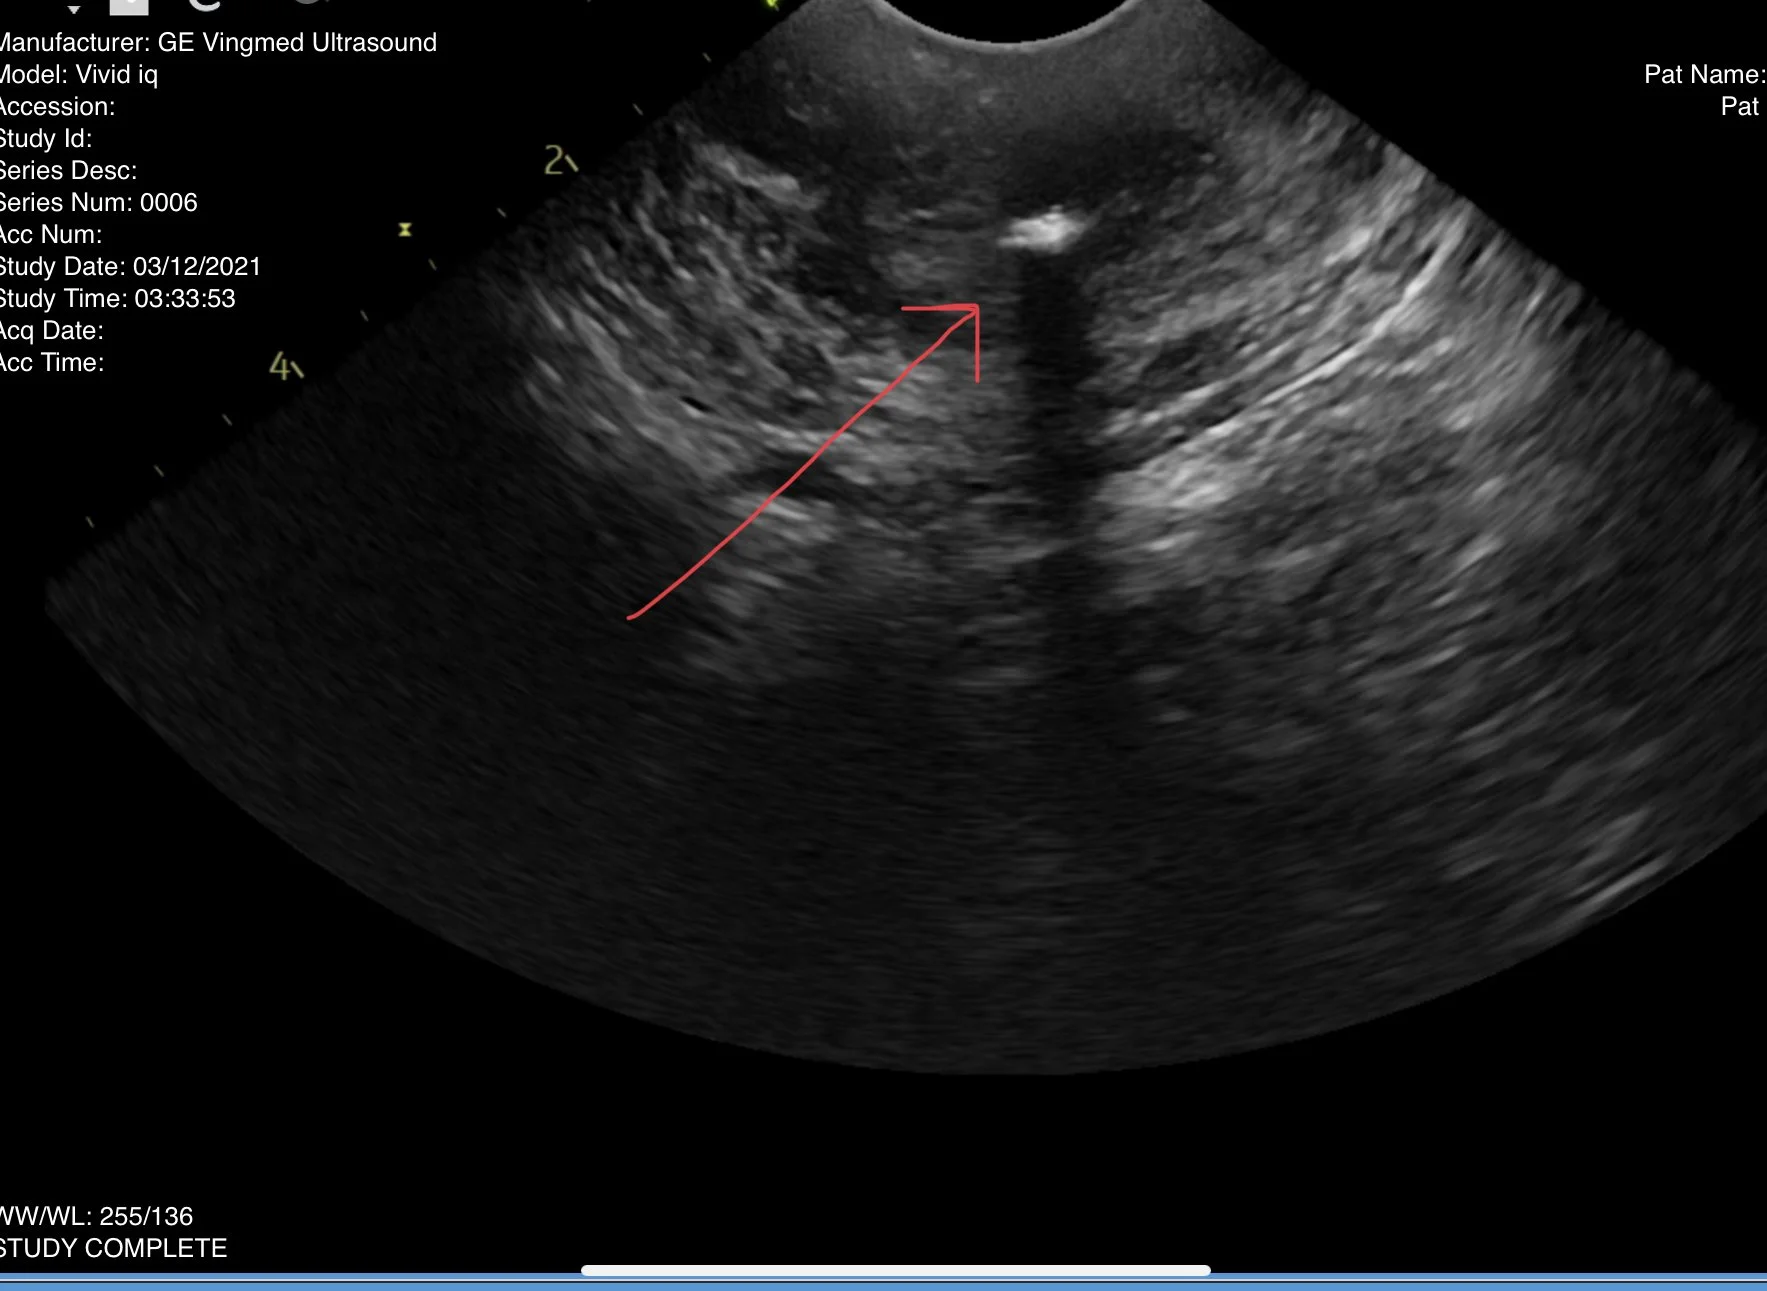

Internal organs such as the liver, kidneys, spleen

Other – other areas of concern that may be evaluated by ultrasound

Ultrasound Examination